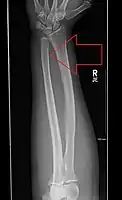

Side view of bowing fractured radius and ulna

The diagnosis of a forearm fracture is made by first inspecting and then feeling the injured forearm for any obvious deformity and tenderness, with particular attention to the radial head.[2] The type of forearm fracture can be confirmed by an x-ray, usually with views from the front and the side, and must include the wrist and elbow joints.[2]